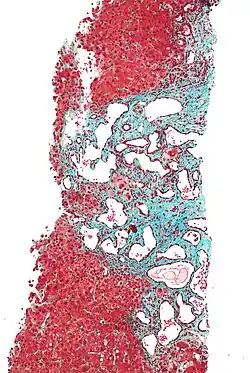

Micrograph of a bile duct hamartoma. Trichrome stain, high magnification Low magnification micrograph of a bile duct hamartoma. Trichrome stain.

Low magnification micrograph of a bile duct hamartoma. Trichrome stain. Gross pathologic appearance of a large bile duct hamartoma.